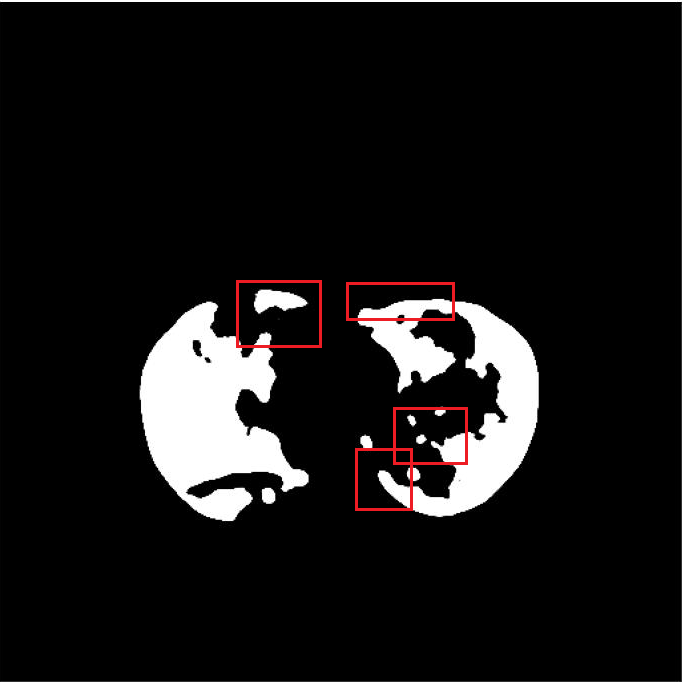

(c) Prediction by FuDSA-Net

(d) Prediction by -Net++

The resultant segmentation map of FuDSA-Net is observed to be relatively more accurate and closer to the corresponding ground truth, as illustrated in Fig. 3.